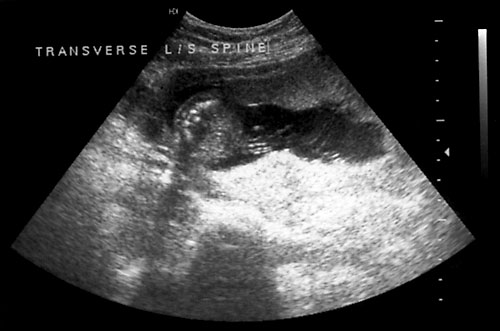

Normal cervical spine at 18 weeks (1). Another normal sagittal view of cervical spine seen in third trimester with folds of fat seen (2). Normal thoracic spine at 18 weeks (3). Normal sagittal view of lumbosacral spine at 18 weeks (4). Normal transverse view of lumbosacral spine at 18 weeks (5). - Extremities (hands/feet)